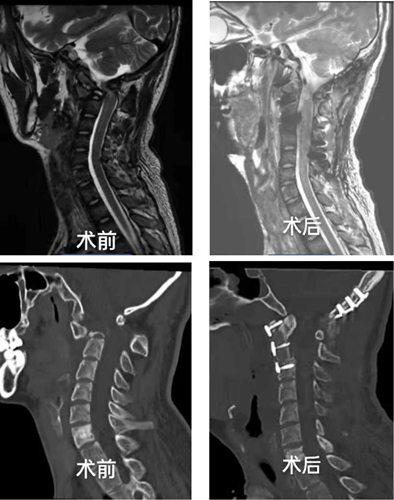

患者高某,23 岁,本是一位帅气小伙,一年前因骨结核造成多处骨质破坏,辗转省内多家三甲医院就诊,疗效不佳且病情逐渐加重。来院就诊时严重消瘦,不能行走,已出现心率快,呼吸急促,四肢不全瘫痪,大、小便困难症状。患者颈部呈右偏屈曲强迫体位,头部被动活动受限,左侧上肢肌力1级,右侧上肢肌力3级,双下肢肌力3级,病理征阳性。影像学显示脊柱、胸骨、肋骨多处病损,尤其是颈2椎体的90%破坏,寰枢关节脱位,导致严重的脊髓受压。

手术过程中,医院MDT团队在耳鼻喉科李和清教授协助下,仰卧位颌下入路显露颈1-3椎体前方,发现颈2椎体大部分骨质已缺损,清除病灶内脓液和干酪样组织,并取自体髂骨植骨填补到颈2 椎体,同时前路钢板的固定,重建颈椎前、中柱的稳定性;前路手术完成后,更换俯卧位,行颈椎后路的枕颈固定、植骨融合稳定脊柱后柱。

术后1周,患者呼吸、心率恢复正常,四肢肌力达到4级,拔出导尿管后,小便功能正常,复查颈椎CT和MRI,显示颈椎脱位已基本复位,颈椎脊髓受压已得到解除。术后2周,四肢肌力已接近5级,能搀扶下地活动。围手术期经过杨驰护士长的优质护理团队精心呵护,患者机体各项指标渐趋正常,病人及家属对治疗结果感到非常满意。